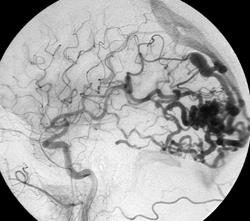

Diagnózis arteriovenosus rendellenességek, mint például, amikor subarahnoialnom vérzés vagy agyi tumor Moz (típusától függően az áramlás).

1. Sebészeti. nyitott műtét, endovaskulyanye beavatkozás

A klasszikus módja, hogy távolítsa el az AVM.